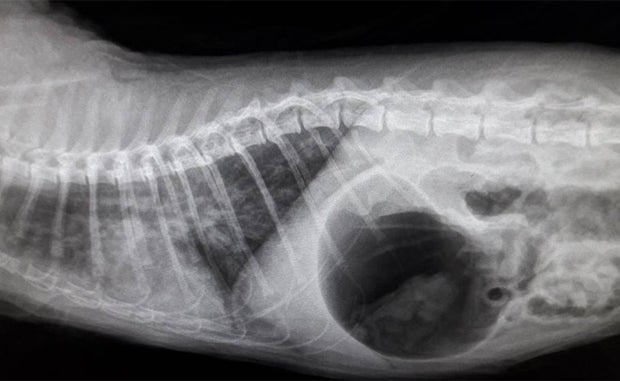

Drama um einen jungen Kater in Wien. Rino hatte sich vergangene Woche in der Waschmaschine versteckt und wäre deshalb fast ums Leben gekommen. Der Besitzer bemerkte den Kater nicht und schaltete die Waschmaschine ein.

Erst nach etwa 30 Minuten bemerkte das Herrl seinen Fehler und versuchte panisch das Bullauge der Waschmaschine zu öffnen, um seinen Kater zu befreien. Schließlich gelang es dem Besitzer, den bei 60 Grad gewaschenen Kater aus der Waschmaschine zu holen und den Tierarzt zu verständigen.

Der Kater befand sich in einem schlechten Zustand und hatte viel heißes Waschmittelwasser in der Lunge. Dem Tiernotarzt gelang es jedoch, den Kater zu retten. Rino konnte nach einigen Tagen in häusliche Pflege entlassen werden.